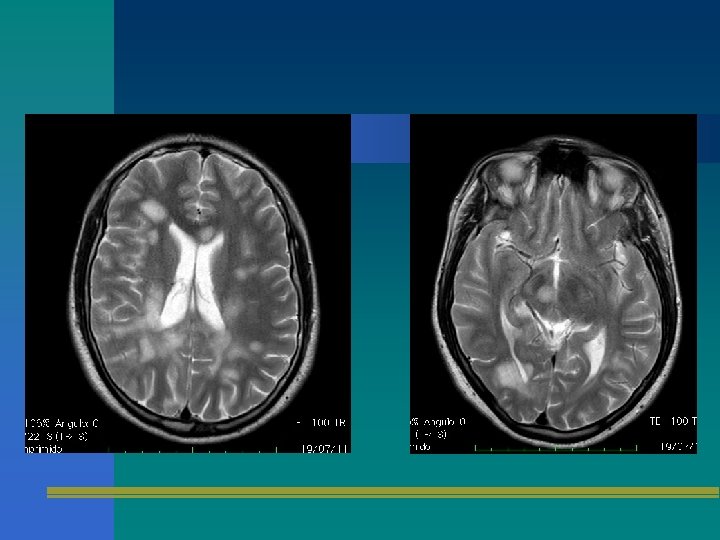

Elementos de apoyo diagnóstico • Resonancia magnética cerebral/espinal • Potenciales evocados – Visuales – Somatosensitivos – Tallo • LCR + Bandas oligoclonales